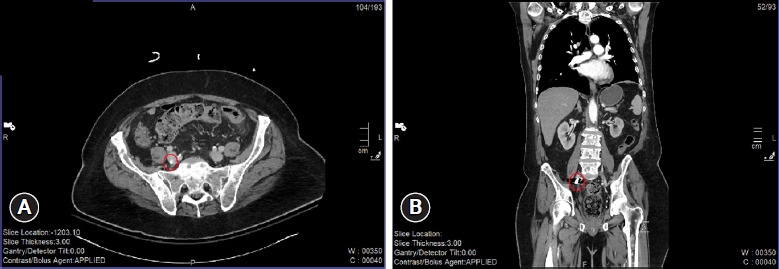

子弹栓塞是枪伤的一种潜在并发症,尤其是在使用低速导弹时。这是因为低速子弹穿过组织时,弹道会明显变慢。可能会出现一种不寻常的飞行形式,即子弹进入血管,但没有足够的动能造成贯穿伤,导致子弹留在血管内。一旦进入血管,子弹就会转移到身体的不同部位,可能会引起缺血、血栓栓塞或感染等并发症。子弹栓塞的处理方法因病例而异,因为每位患者都有独特的身体习惯,这可能导致子弹栓塞的轨迹和目的地出现无限可能。周围血管或组织可能受到额外损伤,子弹也可能栓塞到身体的关键部位。我们在此介绍一名 72 岁男性的病例,他的胸部被一颗低速子弹自残,子弹穿透了心脏右心房。子弹穿过右心房进入静脉血管,进入下腔静脉,最终落在右髂内静脉。经过初步检查和抢救,他拒绝接受进一步的干预和治疗。

Bullet embolism is a potential complication of a gunshot wound, especially with a low-velocity missile. This is because the trajectory of the low-velocity bullet can be significantly slowed as it passes through tissue. An unusual form of travel can occur in which the bullet enters the vasculature but does not have enough kinetic energy to create a through-and-through wound, leading it to remain inside the vasculature. Once inside the vasculature, the bullet could migrate to different parts of the body, potentially causing complications such as ischemia, becoming a source of thromboembolism, or functioning as a nidus for infection. The management of a bullet embolism varies from case to case, as each patient with this issue has a unique body habitus that can result in infinite possibilities of the trajectory and destination of the bullet embolus. Additional damage to surrounding vasculature or tissue can occur, as well as embolization of the bullet to critical areas of the body. Here we present the case of a 72-year-old man who had a self-inflicted gunshot wound to the chest with a low-velocity bullet, which penetrated the right atrium of the heart. It traveled into the venous vasculature through the right atrium, into the inferior vena cava, and eventually settled in the right internal iliac vein. He refused further intervention and management after initial workup and resuscitation.